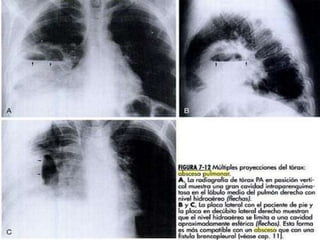

 Patología que produce atrapamiento de aire a

nivel de parénquima pulmonar con dilatación

alveolar, parcial o total con atrofia y perdida

de elasticidad de sus paredes.

 Expresa el estado de menor densidad del

parénquima pulmonar.

 Hiperclaridad circunscrita

 Forma, tamaño y contornos variables

 Nivel horizontal (liquido y gas en su interior)

 Enfisema pulmonar

 Distensión permanente del parénquima

pulmonar con atrapamiento de aire y ruptura

de las paredes alveolares.

 Hipersonoro (tipo timpanico)

 Costillas en disposición horizontal

 Aplanamiento de cúpulas diafragmáticas

 Los ángulos costo y condrofrenicos se hacen

obtusos o rectos

 Aumento del espacio retroesternal

 Parénquima pulmonar hiperluminoso